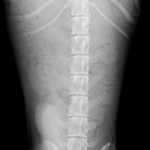

腹部 X 線写真では、肥大した前立腺が下腹部の軟組織塊として観察される。通常のサイズは骨盤入口の幅の 50% 未満である。慢性前立腺炎患者の中には、実質の石灰化が見られる場合もある。腰下リンパ節に腫大があれば前立腺の腫瘍を疑う必要がある。